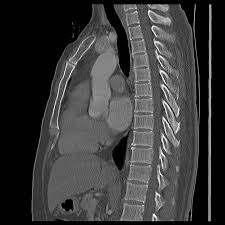

Fractured Sternum Injury Boston Chest Injury Lawyer

Fractured Sternum Injury Boston Chest Injury Lawyer from burnsjainlaw.com